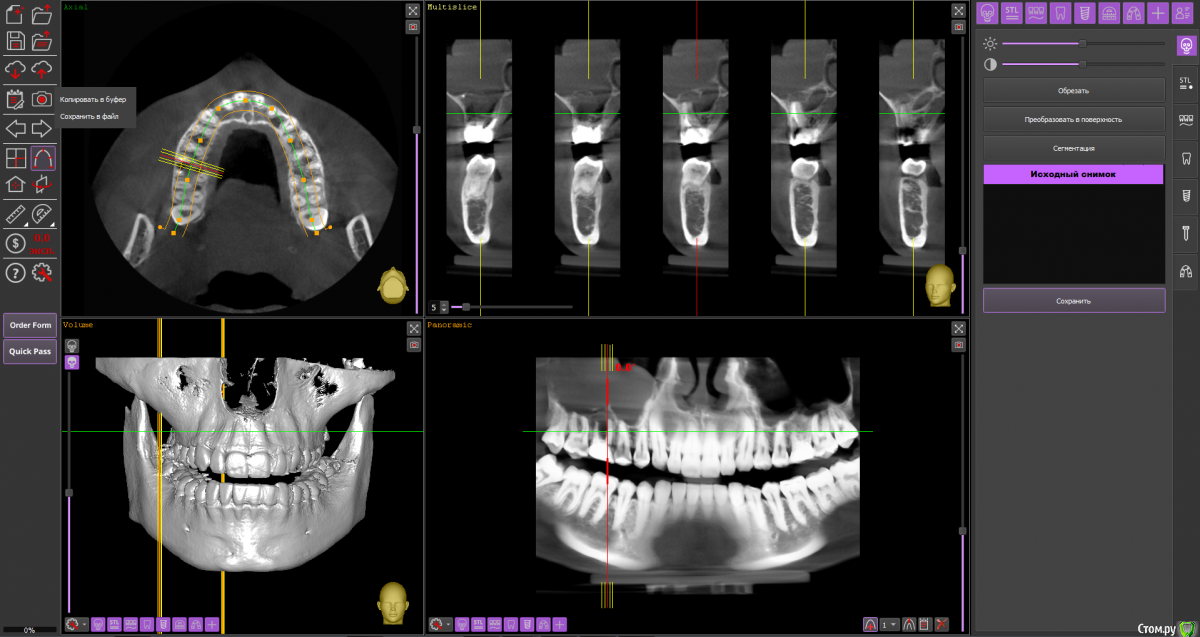

Ольга Вовк Опубликовано 10 февраля, 2021 Поделиться Опубликовано 10 февраля, 2021 Добрый день! Очень прошу помочь по таким вопросам:1. Верхняя шестерка справа - там киста перешедшая в гайморову пазуху (узнала это 4 месяца назад). Зуб ныл 2 года назад, тогда врач просто прописала Аугментин. Все прошло, но опять начал поднывать неделю назад (сейчас опять прошло). Была на консультации, сказали вырывать и прочищать пазуху нужно сейчас, и по приезду уже дальше разбираться. Как лучше быть, если я через неделю уезжаю на 4.5 месяца в страну, где никак не смогу продолжить лечение, а значит ставлю на паузу все на этот период.1. Удалить зуб сейчас, чтоб он зажил и через 4.5 месяца приехав сделать синус лифтинг и ставить имплант, или же ждать это время не удаляя зуб? 2. Не разрушится ли если сейчас не вырвать полностью костная ткань? 3. Можно ли не ставить имлпант, а сдвинуть 7 и 8 зуб к 5ому? Также вопрос по верхней шестерке слева - можно ли ее перелечить под микроскопом, или нужно делать резекцию? Разные врачи сделали разные выводы по нему Ссылка на архив файлов панорамного КТ - http://fayloobmennik.cloud/7414975 Спасибо вам, очень надеюсь на совет Ссылка на комментарий

wladdX Опубликовано 10 февраля, 2021 Поделиться Опубликовано 10 февраля, 2021 (изменено) Зуб 16, мне кажется, лучше удалить до отъезда. Насчёт ортодонтического перемещения 8-го и 7-го на место 6-го, необходимо с ортодонтом очно пообщаться, но на мой взгляд, хирургическое лечение будет более предсказуемым.Зуб 26 может оказаться непростым для эндодонтиста, но если доктор берётся и Вы ему доверяете, то начать стоит с повторного эндодонтического лечения с увеличением. Изменено 10 февраля, 2021 пользователем wladdX 2 Ссылка на комментарий

Ольга Вовк Опубликовано 10 февраля, 2021 Автор Поделиться Опубликовано 10 февраля, 2021 16_1.png 16_2.png 16_3.png 26_1.png 26_2.png 26_3.png 26_4.png Зуб 16, мне кажется, лучше удалить до отъезда. Насчёт ортодонтического перемещения 8-го и 7-го на место 6-го, необходимо с ортодонтом очно пообщаться, но на мой взгляд, хирургическое лечение будет более предсказуемым.Зуб 26 может оказаться непростым для эндодонтиста, но если доктор берётся и Вы ему доверяете, то начать стоит с повторного эндодонтического лечения с увеличением.Спасибо вам огромное! Я так понимаю, что если не удалить сейчас, то тогда к приезду (3 июля) уже совсем костной ткани не останется? Просто если сейчас удалить и будут осложнения, или соустье в гайморову, то я уеду и там не знаю что буду делать в такой ситуации(( Ссылка на комментарий